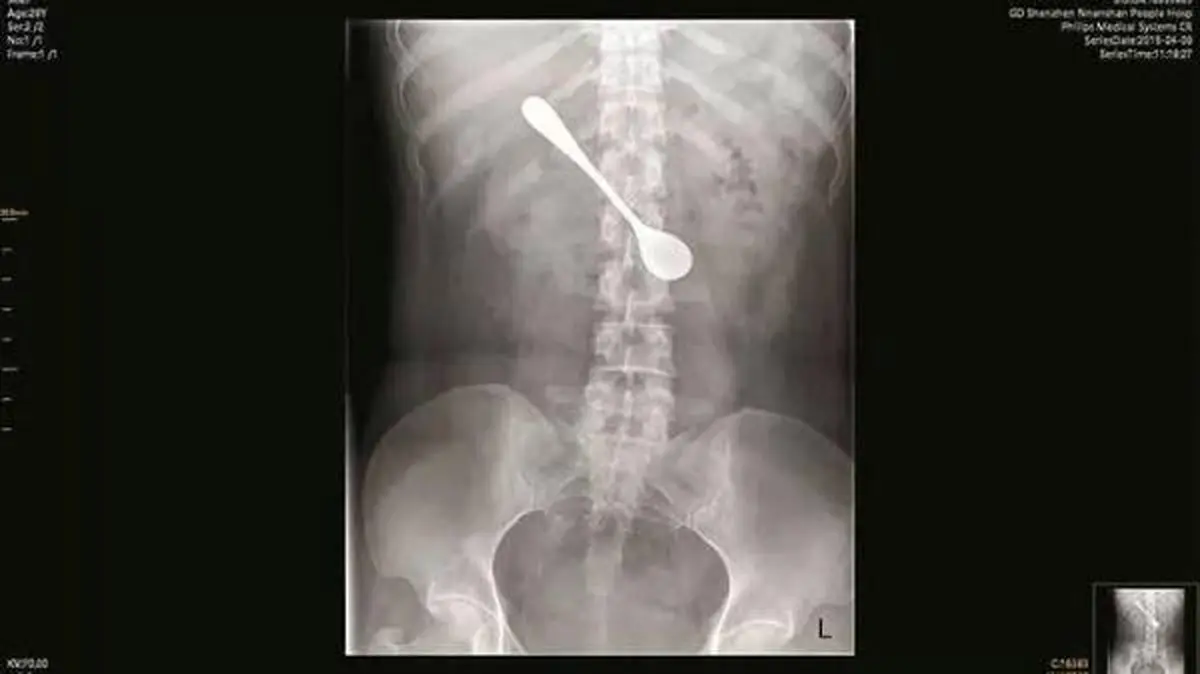

عکس / قاشق 13 سانتی در معده یک زن !

حوادث رکنا: قاشق 13 سانتی متری از شکم یک زن چینی خارج شد.

از قرار معلوم زن جوان برای بیرون آوردن تیغ ماهی از گلویش تصمیم گرفت تا قاشقی را قورت دهد تا استخوان خارج شود اما اتفاقی که به صورت تصادفی برای او رخ داد او را تا مرز مردن پیش برد.

زن جوان که لی لی نام دارد پس از مدتی که درد در ناحیه معده اش شروع شد تصمیم گرفت تا با مراجعه به پزشک علت آن را جویا شود که پزشکان با آندوسکوپی و معاینات متوجه قاشق 13 سانتی داخل معده زن جوان شدند.

به گفته پزشکان، قاشق فلزی موجب ورم و فرسایش بیمار شده بود، اما توانستند آن را از بین ببرند و پس از درمان اوضاع بیمار رو به بهبودی رفت.